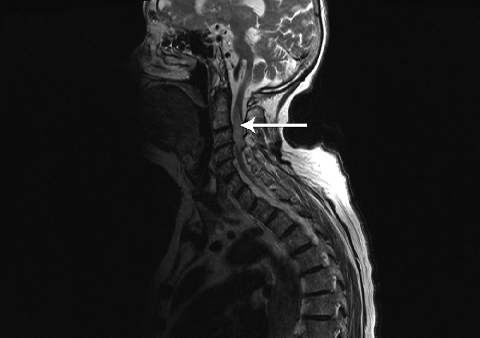

Diagnosing HZM can be challenging. The importance of a careful clinical assessment to establish the likelihood of this diagnosis and the level of the spinal cord damage, in combination with confirmatory magnetic resonance imaging (MRI)7cannot be overstated. MRI not only provides information about the site but also the extent of spinal cord involvement, and excludes other possible diagnoses. In our patient, HZM was diagnosed based on the temporal relationship of myelopathy to the rash and MRI findings. Although the area of the spinal cord that was involved on the MRI scan was less extensive than that affected by the herpetic rash, we do not see this as clinically inconsistent.